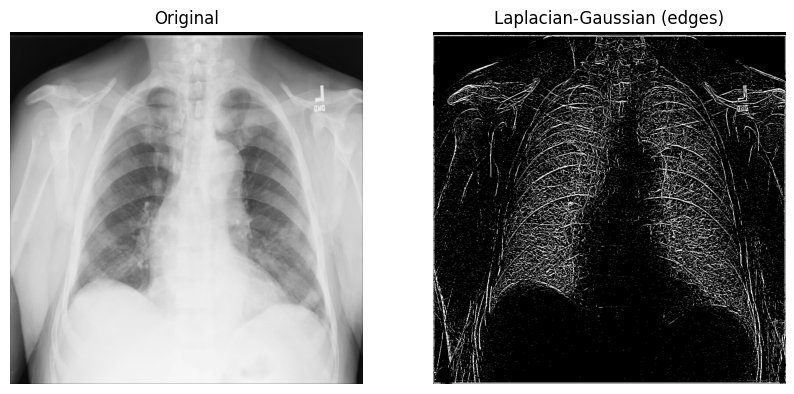

具有高斯二阶导数的拉普拉斯滤波器#

让我们从 使用高斯二阶导数的 n维拉普拉斯滤波器(“拉普拉斯高斯”) 开始。这种拉普拉斯方法侧重于值强度快速变化的像素,并与高斯平滑相结合以 消除噪声。让我们来看看它如何在分析 2D X 射线图像时发挥作用。

拉普拉斯-高斯滤波器的实现相对简单:1)

ndimage从SciPy导入模块; 2)scipy.ndimage.gaussian_laplace()使用 sigma(标量)参数进行调用,该参数会影响高斯滤波器的标准差(您将1在下面的示例中使用):

显示原始 X 射线和带有拉普拉斯高斯滤波器的 X 射线:

fig, axes = plt.subplots(nrows=1, ncols=2, figsize=(10, 10))

axes[0].set_title("Original")

axes[0].imshow(xray_image, cmap="gray")

axes[1].set_title("Laplacian-Gaussian (edges)")

axes[1].imshow(xray_image_laplace_gaussian, cmap="gray")

for i in axes:

i.axis("off")

plt.show()